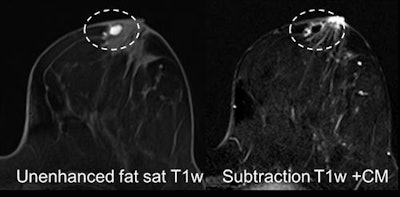

Case 1: On a 44-year-old woman, MRI was performed for problem-solving due to suspicious lesion left side retroareolar region, several similar lesions on ultrasound, appearing hypoechogenic with dorsal acoustic shadowing. MRI shows dehydrated proteinaceous fluid on precontrast T1-weighted imaging, after contrast media injection a periductal enhancement. This is typical periductal mastitis and cancer could be excluded. All images courtesy of Dr. Pascal Baltzer.Speaking to AuntMinnieEurope.com, he confirmed the survey had thrown up surprising results. Given his experience of working in Germany and Austria, and close collaborations with Italian colleagues, Baltzer noticed there were significant differences, both in application and reimbursement of MRI. This prompted him to send an online survey to EUSOBI members between 1 November and 31 December 2015.